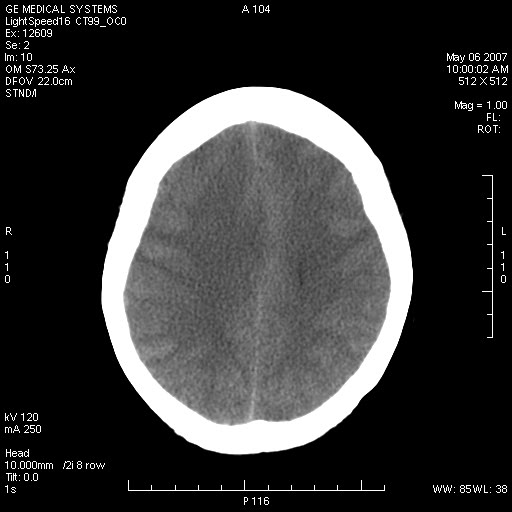

女,60岁,头痛6~7天。

右颞叶巨大高低混杂密度肿块,病灶内可见多发条块状钙化影,占位效应明显,中线结构显著左偏,肿块周围水肿明显,临近颅骨吸收变薄,边缘光整,考虑1少枝胶质瘤2脑膜瘤3转移瘤4室管膜瘤5淋巴瘤6三叉神经瘤(多多益善)合并镰下疝

右颞叶混杂密度,累及右额叶。其内可见条片状钙化及斑片状略高密度,周围少量水肿,右颞骨吸收变薄,中线结构左移。考虑1少突胶质瘤。2脑膜瘤。合并瘤卒中。建议增强扫描。

右额、颞叶巨大高低混杂密度肿块,病灶内可见多发条块状钙化影,占位效应明显,中线结构显著左偏,肿块周围水肿明显,临近颅骨吸收变薄,边缘光整。

考虑:1、少枝胶质瘤;

2、脑膜瘤?

3、镰下疝;

4、建议增强扫描进一步检查。